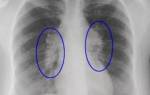

Для визуализации патологического процесса назначается рентгенологическое исследование органов грудной клетки, которое позволяет обнаружить изменения в легких. Обнаруживаются изменения с обеих сторон, преимущественно в нижних отделах легких.

Отмечаются усиление и деформация легочного рисунка, постепенно формируется картина так называемого «сотового легкого», которое характеризуется образованием кольцевых теней диаметром 3 – 7 мм со стенками толщиной до 3 мм, что в некоторой мере напоминает пчелиные соты.